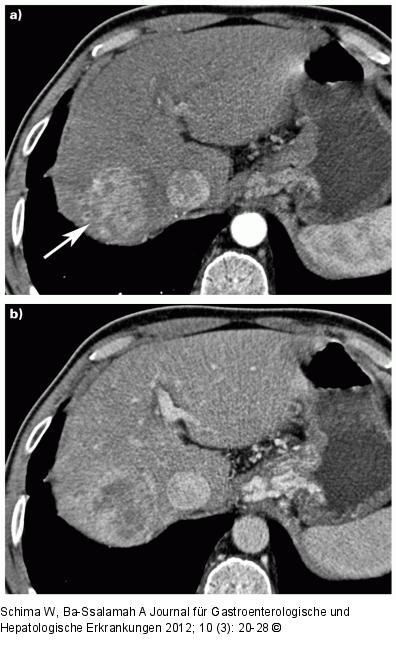

Abbildung 1: HCC Hepatozelluläres Karzinom (HCC). (a) Die kontrastmittelverstärkte MDCT zeigt typischerweise in der arteriellen Phase eine verstärkte Kontrastmittelaufnahme des HCC (Pfeil) im rechten Leberlappen, neben der V. cava inferior. (b) In der venösen Phase zeigt sich ein rascher Wash-out, was typisch für ein HCC ist. |

Hepatozelluläres Karzinom (HCC). (a) Die kontrastmittelverstärkte MDCT zeigt typischerweise in der arteriellen Phase eine verstärkte Kontrastmittelaufnahme des HCC (Pfeil) im rechten Leberlappen, neben der V. cava inferior. (b) In der venösen Phase zeigt sich ein rascher Wash-out, was typisch für ein HCC ist. |